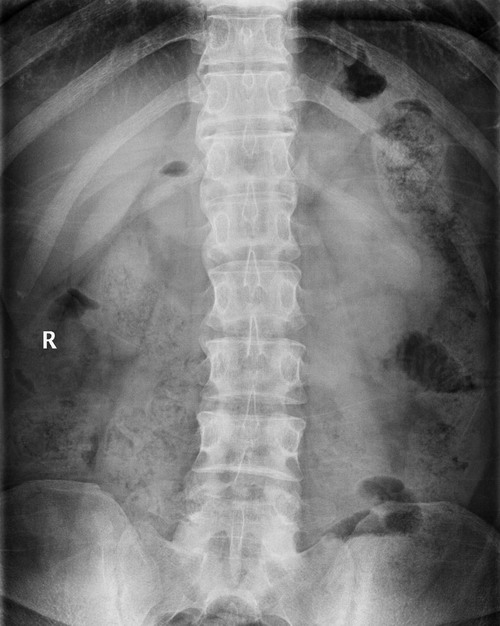

标题: X7679:男,25岁,腰部疼痛查因 [打印本页]

标题: X7679:男,25岁,腰部疼痛查因

1)强直性脊柱炎可能性大;建议查hla-b27。2)l4前上缘许莫氏结节。

不用查了,脊柱都呈竹节样改变了。

t12-l1、l1-l2、l2-l3椎体前缘骨桥形成,但骶髂关节未见明显异常。虽然as发病年龄较早,dish好发于50岁之后,但本例还是考虑弥漫性特发性骨肥厚(dish)。l4前上缘骨软骨炎。

as发病年龄10-40岁,好发部位 骶髂关节 ;as韧带走行较平直,有骶髂关节有改变

dish发病年龄50岁以后, 好发部位 脊柱;一般有背痛而不放射,可伴强直,后纵韧带及椎关节侧韧带广泛钙化,呈水波样。

诊断标准包括以下3条标准:

(1)连续4个或4个以上椎体的前外侧流水样钙化,伴椎体和椎间盘结合部的骨化;

(2)受累部位椎间盘的高度无明显塌陷;

(3)骶髂关节无侵蚀、硬化或骨性融合。